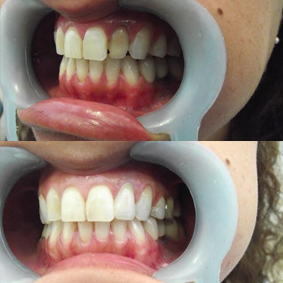

Replace teeth that have been lost with the passage of the years restoring functionality and aesthetics to your mouth.A dental implant is a cylinder shaped dental root manufactured alloplastic material (usually titanium) which is surgically implanted under the gums inside the maxillary or mandibular bone; once placed and osseointegrated, the dentist will place upon them crowns or fixed bridges that will replace the teeth lost, then the implant helps us provide retention and support a fixed or removable dental prosthesis.

The Dental implant merges with the bone of the jaw thus creating a stable support for the fake teeth, dentures, bridges and individual crowns placed upon implants will not move inside the mouth, providing comfort and safety when it comes to chewing and speaking.

With dental implants, it is not necessary to wear down adjacent teeth so that they hold to the replacement teeth, do not produce irritations, nausea nor must be attached to teeth on both sides of the gap as it usually happens with prostheses or common bridges.